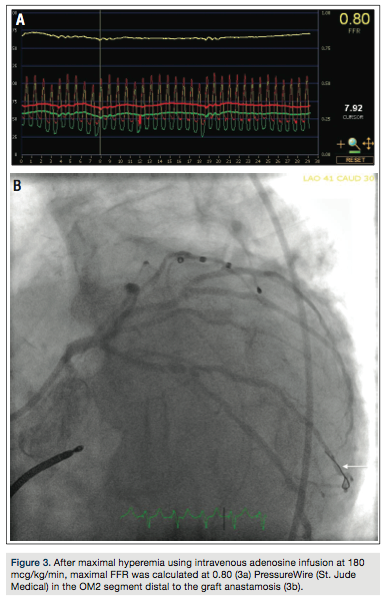

80% stenosis at the second and third obtuse marginal (OM) branch bifurcation, with competitive flow noted in the distal OM2 branch (Figure 1). Selective graft angiography of the left internal mammary artery (LIMA) to the mid left anterior descending artery demonstrated a patent jump graft from LIMA to OM2 with a distal anastamotic 60-70% stenosis (Figure 2). Due to concern for the adequacy of perfusion of the OM2 segment via the native circulation or the jump graft, a strategy to measure the fractional flow reserve (FFR) in the distal OM2 branch was pursued. After maximal hyperemia using intravenous adenosine infusion at 180 mcg/kg/min, maximal FFR was calculated at 0.80 (Figure 3a) with a PressureWire (St. Jude

Medical) in the OM2 segment distal to the graft anastamosis (Figure 3b). A pullback FFR revealed a maximal value at 0.75 (Figure 4a) with the PressureWire wire in the OM2 segment proximal to the graft anastamosis (Figure 4b). Due to the suggestion of borderline perfusion in the distal OM2 segment despite the bypass graft, percutaneous coronary intervention (PCI) of the mid left circumflex artery was performed using a Veriflex 3.0 x 16 mm bare metal stent (Boston Scientific) with excellent angiographic result and brisk retrograde flow through the bypass graft (Figure 5).